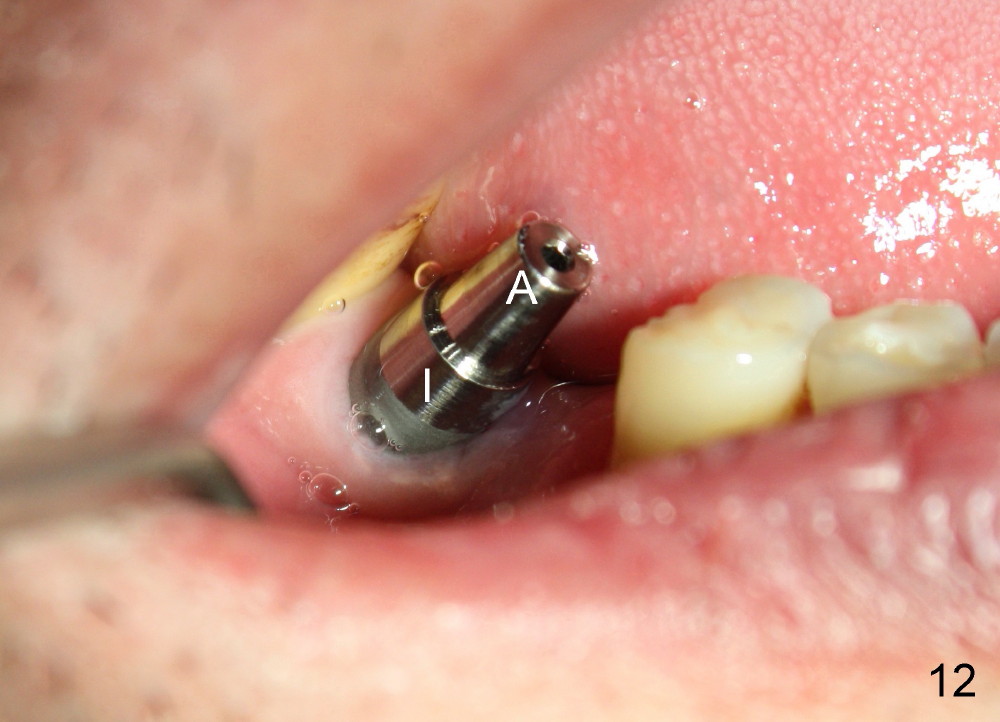

When the perio dressing is removed in office 24 days postop (Fig.9), the rough surface of the implant (R) is exposed buccally.  Normally the smooth surface should contact the gingiva (S).   Lingually implant/gingiva position is within normal limit (Fig.10).  The patient returns for restoration 4 months postop (Fig.11,12).  There is bone formation in the mesial socket and new bone appears to have grown toward the implant (Fig.11 <).  A straight abutment appears to be in the middle of the edentulous space (Fig.12 A).   But it is difficult to seat the crown.  Three months post cementation, the patient complains of food impaction mesially (Fig.10 ^), although bone density continues to increase in the mesial socket and there is no mesial coronal thread exposure (*).  Retrospectively the implant should be tried to be placed in the septum as much as possible to have a favorable restorative axis (Fig.14).  The crown is re-fabricated with larger mesial contact area.  It is temporarily cemented because of slightly loose distal contact (Fig.15).  A few days later, the patient requests permanent cementation, because although the distal contact is loose, it is easy to remove food.  Mesial food impaction is less likely, but it is more difficult to be removed.